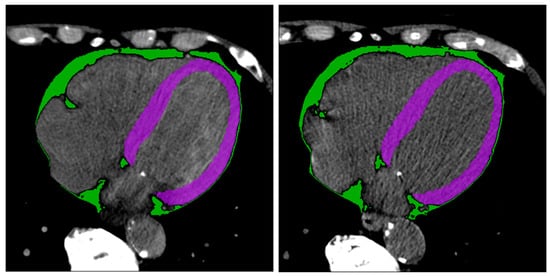

Figure 3 shows two example masks of the myocardium and epicardial fat in intra-patient TNC and VNC images. The number of radiomics features extracted in each reconstruction for every anatomical structure is 105. The complete list of extracted features is available in Figure 4 (x-axis). ICC values computed for VNC and TNC reconstructions of myocardium and epicardial fat are available in Figure 4 and Figure 5. The values of the ICC coefficients are ordered in a descending fashion to better comprehend which features are more correlated (i.e., remain more stable) between VNC and TNC acquisitions. In each Figure, the blue square identifies the related ICC value, which is also reported, and the extremities of vertical lines crossing each square represent the lower and upper bounds. Figure 4 presents the ICC values computed for the features extracted from the myocardium. Similarly, Figure 5 displays the ordered ICC values computed for the features extracted for the epicardial fat.

Figure 3. Segmentation results. Segmentation of myocardium (in green) and epicardial fat (in purple) in intra-patient TNC and VNC images (first and second subfigure, respectively). Figures are visualized with window center 97 and window width equal to 215.